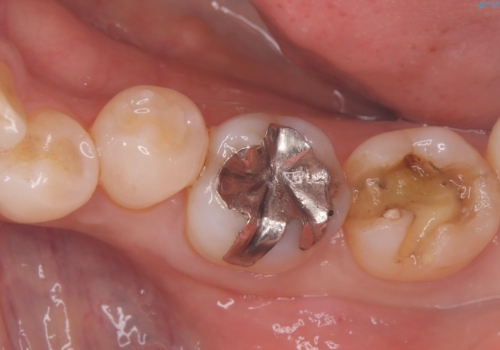

- 主訴:左上真ん中らへんの歯が欠けてしみるので治したい

審美性、適合性の良いセラミックインレーでのやり替えとなりました。

左上4近心に実質欠損を認め、遠心から咬合面にかけてはCR修復が施されていたため、MODインレー窩洞としました。